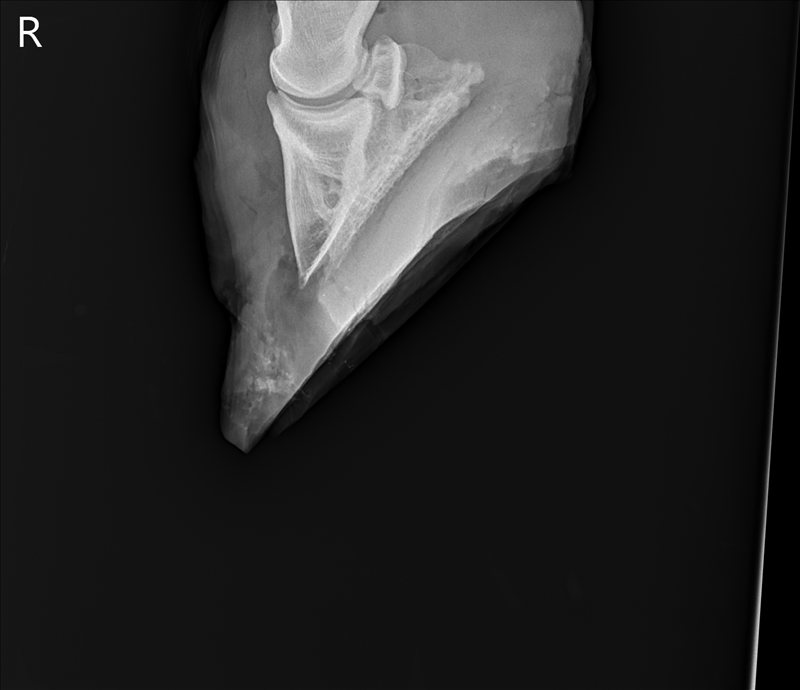

The surgeon was incredibly nice, and pointed out the sequestrum – technical term for a foreign object causing infection, in this case the bone chip – as well as how they’d get in there. He was glad that Tris’s abscess had come out the toe, too, because that gave him a clear channel to go through. He explained that he would make a hole about the size of a quarter, then go in through there with a tool that looked a lot like a very small, very sharp ice cream scoop. He’d remove the chip, and then scrape at the bone until he removed all the necrotic bone and debrided back to health bone. He described the sound of healthy bone as “crisp.” (Ew.)

![]() |

| Pre-surgery x-ray with the vet’s labels. |